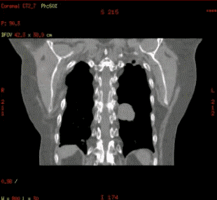

于是,我可以走进更多的科室,当然我的老家影像科,我也是常回来看看,我可以达到和诊断CT一样的空间分辨率和密度分辨率,因为我有一颗强劲的心脏,一天轻松完成百余例患者扫描。

在放射治疗科,我可以进行放疗患者CT定位扫描,我可以不依靠第三方厂家,自己做四维呼吸门控扫描,我可以自动去除患者金属伪影,我的老搭档SIM兄弟可以自动勾画正常器官外轮廓,支持在四维CT图像上实时定义修改结构,可以存储为RT DICOM格式发送给TPS。